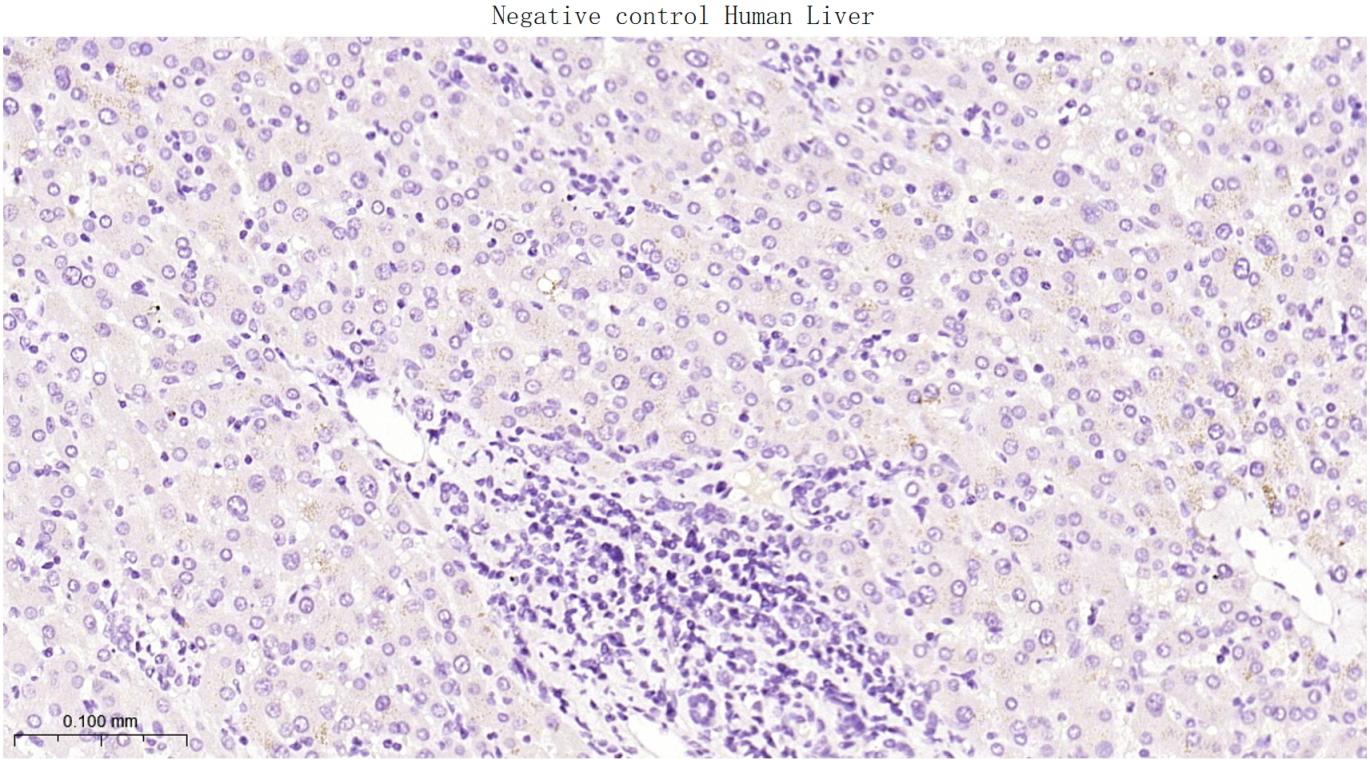

(Negative control) Paraformaldehyde-fixed, paraffin embedded Human Liver; Antigen retrieval by boiling in sodium citrate buffer (pH6.0) for 15 min; Antibody incubation with FAP Monoclonal Antibody, Unconjugated(bsm-63060R) at 1:200 overnight at 4°C, followed by conjugation to the bs-0295G-HRP and DAB (C-0010) staining.